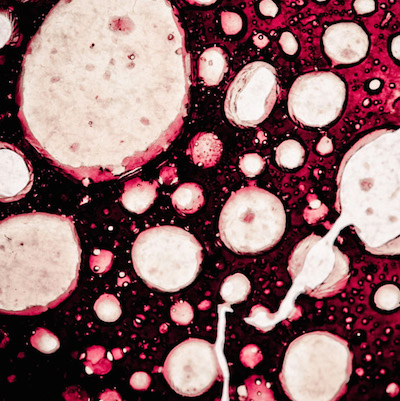

Исследователями из Колумбийского университета, что в городе Нью-Йорк совместно с учеными Норвежского технологического университета провели такой эксперимент на мышах. Клетки опухоли желудка останавливают свой рост благодаря веществам, которые есть в ботоксе. Препараты ботулотоксина способны замедлять воздействие раковых клеток только на начальной стадии развития новообразования.